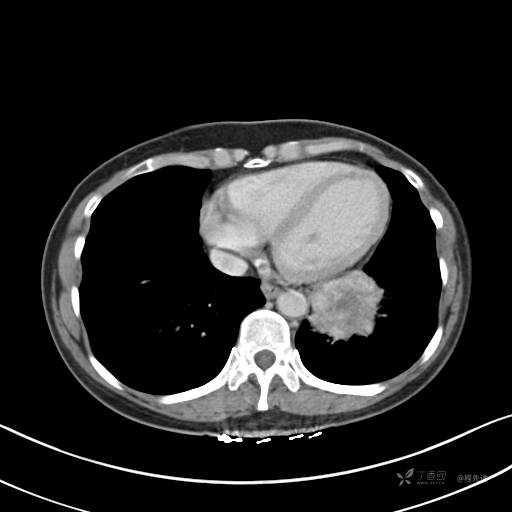

冠状位重建

CT值:平扫:31HU,动脉期:74HU,静脉期:84HU